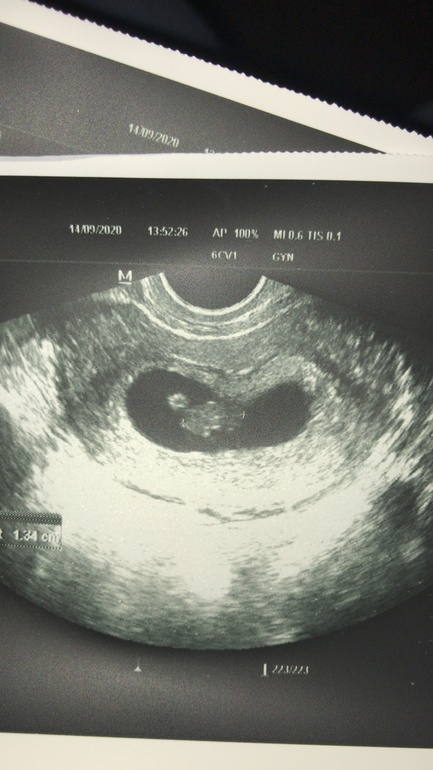

Валерия в Зачатие 5 лет Все отлично ! Беременность- 1 триместр ( только до 10 недель) Была сегодня на узи,у нас все отлично Ктр 13,свд 26,жм 4,5 Сердечко бьется вовсю 🙏 Посмотрите еще 20 записей на эту тему Отменить Ответить Алена Поздравляю🎉🎊 14.09.2020 Ответить Фокси а какой у вас акушерский срок?))))) Поздравляю!!)))) 14.09.2020 Ответить Валерия Акушерский 7+6 По узи получилось 7+4 14.09.2020 Ответить Фокси спасибо за ответ))) растите здоровыми!!!! 14.09.2020 Ответить Валерия Спасибо 🙏 14.09.2020 Ответить Оксана Ну вот и отлично, теперь раслабляемся и радуемся положению 14.09.2020 Ответить Валерия Да,теперь можно немного выдохнуть 🙏 14.09.2020 Ответить Счастье любит тишину Растите крепкими и здоровенькими🥰 14.09.2020 Ответить Валерия Спасибо большое☺️ 🙏 14.09.2020 Ответить Беременность 🤰 ТТГ Узи ♥️ Чаты Беременных Выберите чат: Январята-2026 Февралята-2026 Мартята-2026 Апрелята-2026 Майчата-2026 Июнята-2026 Июлята-2026 Августята-2026